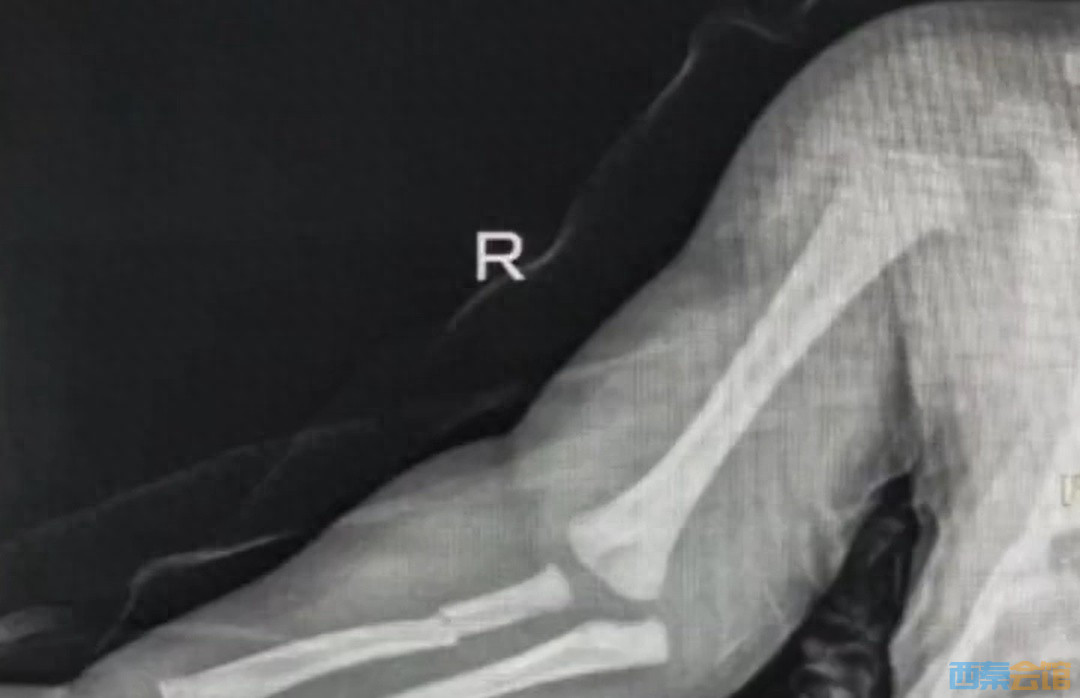

2月25日,广州市妇女儿童医疗中心医生反映一名15天大的婴儿双上肢多处骨折。

针对网民怀疑婴儿是否因虐待导致骨折,当事医生表示,医院医务部已介入跟进。

2月26日,医院医务部工作人员表示,经核实,婴儿系坠床导致骨折,未受虐待,经手术恢复良好。辖区派出所工作人员表示,未接到相关情况报警。

视频截图